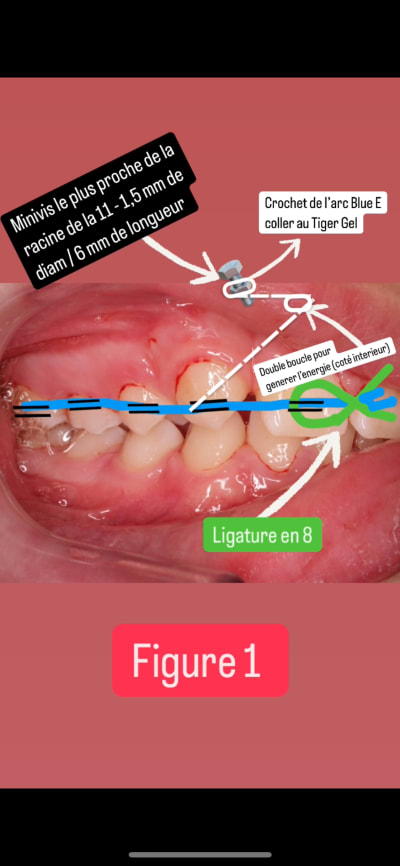

Je vais tenter de me prêter à votre exercice avec les faibles données scientifiques que j’ai sur le sujet, désolé pour le pavé ça m’aide haha.

Concernant l’option des minivis, vous soulevez une très bonne question sur la gestion verticale, surtout à cause du contact limité bout à bout des incisives.

Finalement, je n’aime pas la technique de mésialisation indirecte avec les minivis pour ce cas de figure (et c’est pour ça que l’individualisation en ortho est importante : ne jamais standardiser un cas ! Ce que j’ai fait sans réfléchir… désolé).

Dans ce cas précis :

- Si nous mésialons la canine sans rien attacher, nous aurons surtout du “rabbitting” coronaire (qui donnera une pseudo-égression dans le sens vertical, + qu’une véritable égression), ainsi qu’une déviation du milieu maxillaire. Généralement, la papille retro-inc et l’orientation du frein labial supérieur me servent de repères si je veux monitorer cela.

-> Mais risque d’AI ant (++) donc nan

- Maintenant, si je fais l’erreur que j’ai mentionnée dans mon premier message, même si j’attache et mésialise de façon indirecte, il y a finalement un risque, comme vous l’avez si bien dit, en vue frontale secteur ant. Soit ma ligature en 8 n’est pas totalement bien attachée, ce qui engendrerait un peu de rabbitting et… bim, AI ! Soit elle est bien attachée mais par une méthode non coulissante (dixit Rickets). Dans ce cas, un fort TRV se crée, ce qui risque d’entraîner une instabilité post-traitement des incisives dans l’os… voire une sortie de la racine 🪟, surtt avec tout ce que nous allons mésialer par la suite. De plus l’incisive 11, étant en première ligne face à la méga canine au coef de resistance élevé, subirait beaucoup plus d’effets parasites que les autres dents meme bien ligaturer.

Donc, toujours un risque d’AI, un TRV++… C’est une histoire à mal dormir la nuit. Même si je mets du torque positif dans mon fil, je doute que ce soit suffisant. Et je ne peux pas faire un UA, car je n’ai plus de pilier de traction ensuite.

On a dit que la mésialisation est le mouvement qui requiert le moins de force, étant le plus naturel. (Si une verticalisation nécessite 30 gF, et une vestibularisation en demandera 50 gF). Je pense donc qu’une force de 30 gF maximum sera suffisante. Ce sera donc facile à obtenir avec du Blue Elgiloy plié.

Solution finale :

Étape 1 (photo Figure 1)

1. Arc SS ou TMA 7-7 en 18x25, avec une ligature en 8 de 11 à 26, un peu lâche, car je veux profiter des effets parasites sans créer de déviation maxillaire. En général, cela suffit pour cet objectif.

2. Minivis de 1,5 mm de diamètre et 6 mm de longueur (plus proche de la racine de 11)

3. Bras en Blue Elgiloy 18x25, avec double boucle côté intérieur. La partie horizontale doit être 1,15 fois plus grande que l’espace à fermer entre la canine et l’incisive. J’ajoute une gaine en plastique dessus pour éviter de blesser le patient.

4. Ligature en 8, car même si les effets parasites ne m’inquiètent plus face au risque d’AI, au pire, je risque peu de proversion coronaire → pseudo-ingression → accentuation de l’infra. Je temporise ces effets au maxx avec la ligature et les corrigerai par la suite a l’etape 2 avec les effets parasites contraires (Les mouvements de va-et-vient sont déconseillés, mais ici, ils seront négligeables.)